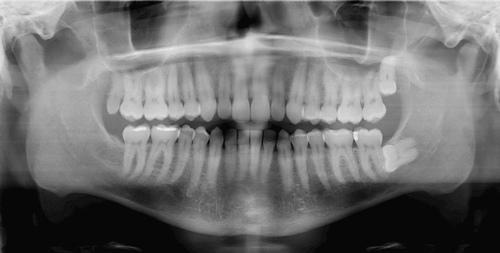

Digital X-Rays

Digital x-rays are a method for dental imaging that allows us to send pictures directly to a computer for storage. In just a few moments, we can view the digitally perfect images and share them with you on a monitor so you can see exactly what we see.

Digital x-rays are safer for you because they significantly reduce your exposure to radiation. State-of-the-art digital images are also better for the environment since we don’t have to worry about safely disposing of potentially hazardous materials used with traditional film x-rays. Digital images can also be sent electronically to a specialist or a new dentist if you move.